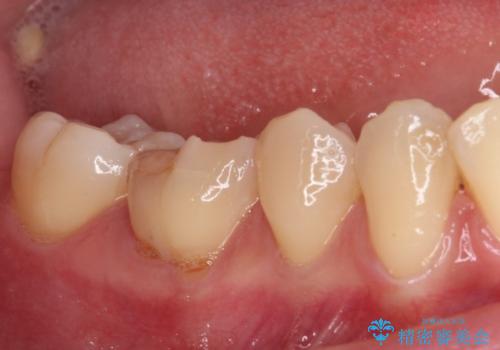

- 奥歯が食事中に歯が欠けて、しみて痛いとのことで来院された患者様です。

レントゲン写真からも、舌側に大きな虫歯があることが分かりました。

症状から神経を取り除く可能性も考慮し、オールセラミッククラウンにて補綴治療することとしました。